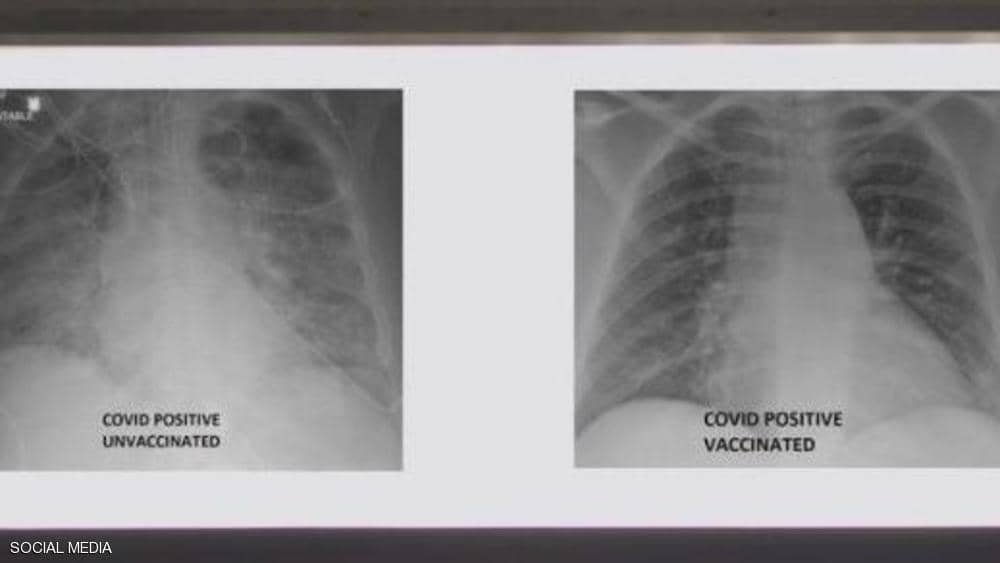

الفرق بين رئتي شخص أخذ لقاح كورونا وآخر لم يحصل عليه.. صورة أشعة

أظهرت صور الأشعة السينية أن رئتي الشخص غير الملقح، المصاب بفيروس كورونا كانت بيضاء بصورة شبه كاملة تعرف بـ «عتامة الرئة» مما يعني أنها كانت غارقة في الفيروس، في حين برزت صور رئتي الشخص الآخر ببيضاء أقل.

وتعني صورة الأول أيضا نقصا في دخول الهواء إلى رئتيه، فيما تعني لدى الثاني أن الهواء يتدفق بسهولة علاوة على أن رئتيه خاليتين من الوباء، حسبما نقلت شبكة «سكاي نيوز» .

وأشار إلى أنه نشر الصور من أجل إظهار الفرق الذي يمكن أن يحدثه اللقاح في رئتي الشخص في حال إصابته بالفيروس.